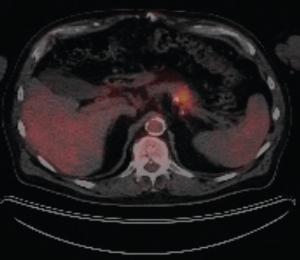

Abstract: Pancreatic neuroendocrine tumors (NETs) are a heterogeneous group of neoplasms. They can be functioning tumors with secretion of a variety of peptide hormones, or nonfunctioning tumors with metastases to the liver at the time of diagnosis. Well-differentiated tumors tend to be slow-growing and characterized by low tumor mutational burden (TMB) and lower propensity to express PD-L1. Hypercalcemia due to malignancy can occur in about 20% to 30% of patients with cancer. The secretion of parathyroid hormone–related protein (PTH-rP) is among the causes of malignant hypercalcemia and has seldom been associated with hypercalcemia of NETs. Although the therapeutic landscape for neuroendocrine neoplasms has evolved substantially over the past decade, the role of immunotherapy has not yet been completely explored in this group of patients. We present a rare case of a metastatic pancreatic NET with high TMB, high PD-L1 tumor proportion score, and high PTH-rP–related hypercalcemia.